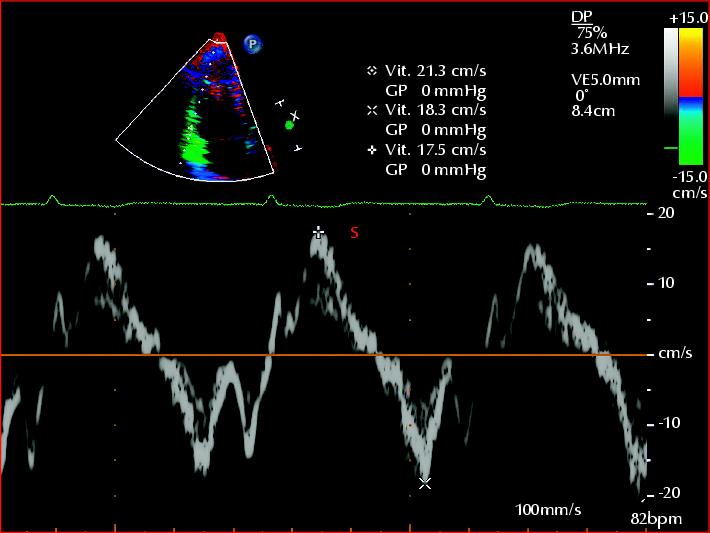

L'augmentation du volume sanguin entraîne celle du volume télédiastolique ventriculaire, d'où un plus grand étirement télédiastolique des cellules musculaires du coeur ce qui aide le coeur défaillant à pomper un volume systolique normal (? figure 9-24b).